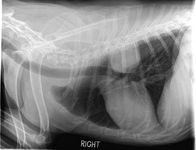

The anatomical location and histologic subtype of primary pulmonary tumors in dogs tend to share similar distribution patterns observed in people. Adenocarcinomas usually present as peripheral, solitary, well-defined masses (Figure 1), while bronchoalveolar carcinomas often manifest as peripheral multifocal densities (Figure 2).5,12,14,18 And primary lung squamous cell carcinomas tend to grow as solitary, hilar masses.10,12,14,18

1. A lateral thoracic radiograph of a 10-year-old castrated male German shepherd presented for evaluation of an intermittent, nonproductive cough of six months' duration. A soft tissue mass effect is identified in the left caudal lung field. The histologic diagnosis was pulmonary adenocarcinoma. (Photograph courtesy of Dr. Laura Garrett.)

The appearance of primary lung tumors varies from a solitary mass (Figure 1) to involvement of an entire lung lobe or multiple lobes (Figure 2), indicating metastatic disease or multicentric pulmonary tumors. Radiographic assessment may be confounded by atelectasis secondary to pneumothorax or pleural effusion. Pleural effusion may result from regional lymph node metastasis, extension of the tumor into the pleura, or concurrent disease such as congestive heart failure or other nonneoplastic processes such as hypertrophic cardiomyopathy, feline infectious peritonitis, and chylothorax.1,14 But keep in mind that pleural effusion devoid of neoplastic cells on cytologic examination does not necessarily rule out primary pulmonary neoplasia.14,19,28